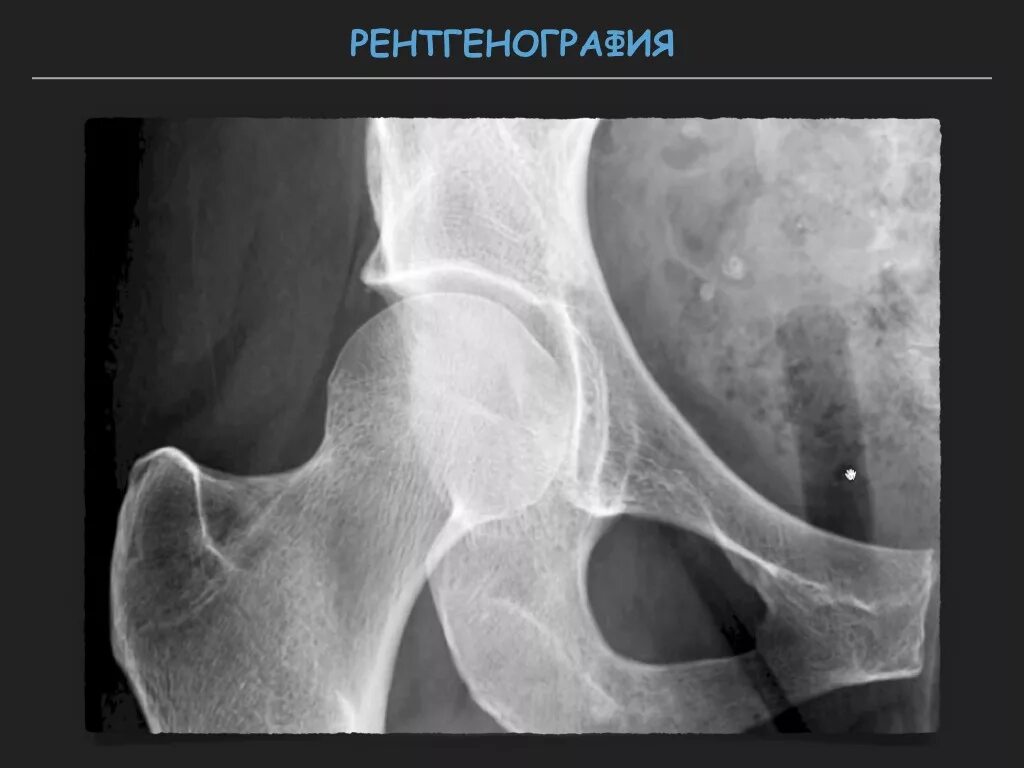

Рентген тазобедренный в двух проекциях